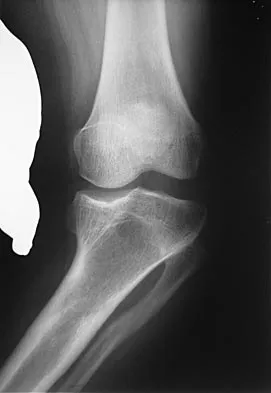

Examination of an obese 3-year-old girl reveals 30 degrees of unilateral genu varum. A radiograph of the involved leg with the patella forward is shown in Figure 10. Management should consist of

The clinical scenario describes infantile tibia vara (Blount's disease). The radiograph shows severe deformity with the characteristic Langenskiold stage 3 changes of the medial proximal tibial metaphysis that distinguish it from physiologic bowing. The preferred treatment is proximal tibiofibular osteotomy with acute correction into slight valgus to unload the damaged area of the physis. This method provides the best results in patients younger than age 4 years. Continued observation would result in progressive deformity. Bracing is most effective in younger children with less severe deformity. Lateral proximal tibial hemiepiphysiodesis relies on growth of the injured medial physis for correction and would result in severe tibial shortening in this young child. Complete epiphysiodesis also produces severe shortening and requires multiple lengthening procedures. Johnston CE II: Infantile tibia vara. Clin Orthop 1990;255:13-23.